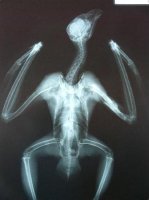

Peñalara presentaba fractura abierta de húmero por disparo.